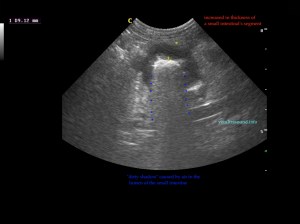

Findings: The ultrasound exam revealed a marked distention of a segment of the small intestine which ended in a narrowed lumen due to a thickened wall. The mesenteric lymph nodes were markendly enlarged and hypoechoic. A fine needle aspirate was performed.

The GIF shows the frames from the normal small intestinal layering to the thickened abnormal wall in a perpendicular view.